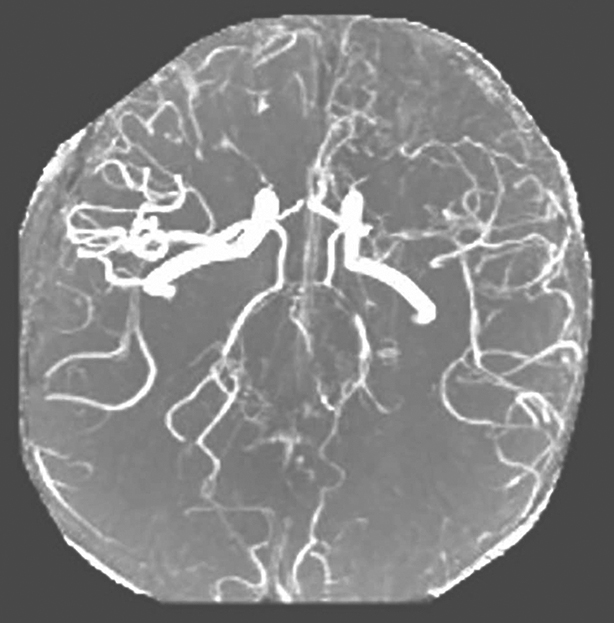

复查CRP、ESR较前上升,头颅MRA(图1)提示血管病变较前加重,考虑病情活动,建议应用TNF-α抑制剂,有助于控制病情发展并协助激素减量,患者及家属拒绝,遂予甲泼尼龙500mg × 3d冲击治疗,后加强免疫抑制剂治疗,方案调整为醋酸泼尼松50mg q.d. +环磷酰胺600mg q.2w. +吗替麦考酚酯1750mg b.i.d.口服,并辅以降压、降糖、保肝等治疗,出院后患者糖皮质激素仍难以减量至35mg q.d.以下,减量后会再发头痛及下肢疼痛,伴有红细胞沉降率及CRP升高。

图1头颅MRA(2015年12月)

左侧大脑中动脉中、重度狭窄或闭塞;双侧大脑前动脉、右侧大脑中动脉、基底动脉及双侧椎动脉、双侧大脑后动脉多发节段性管腔狭窄